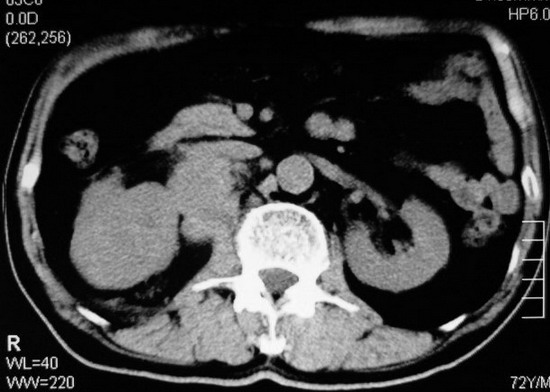

以下是引用杀毒软件在2008-11-17 19:15:00的发言:[br]考虑------右肾癌合并肾静脉---同侧肾上腺受侵可能性大

以下是引用zjzjr在2008-11-17 20:45:00的发言:[br]考虑------右肾癌合并肾静脉---同侧肾上腺受侵可能性大及腹膜后淋巴结转移.